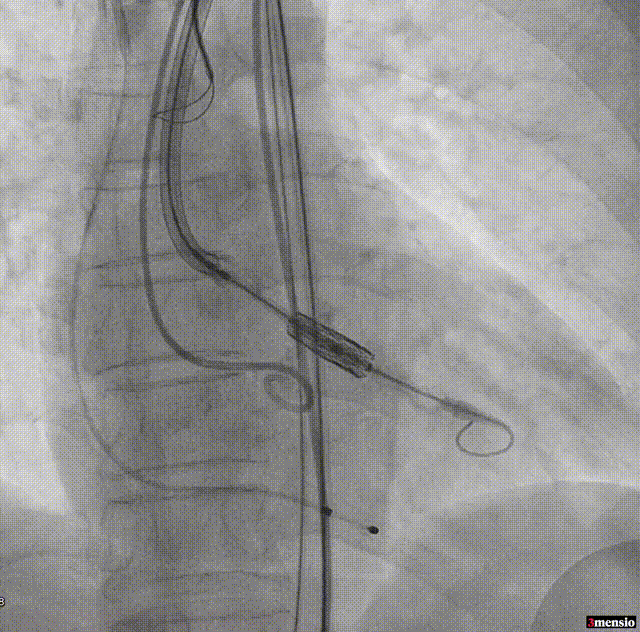

MuguetA™21 mm瓣膜+1cc释放

释放后腰迹明显,轻度瓣周漏,原体积后扩

根部造影显示微量瓣周漏